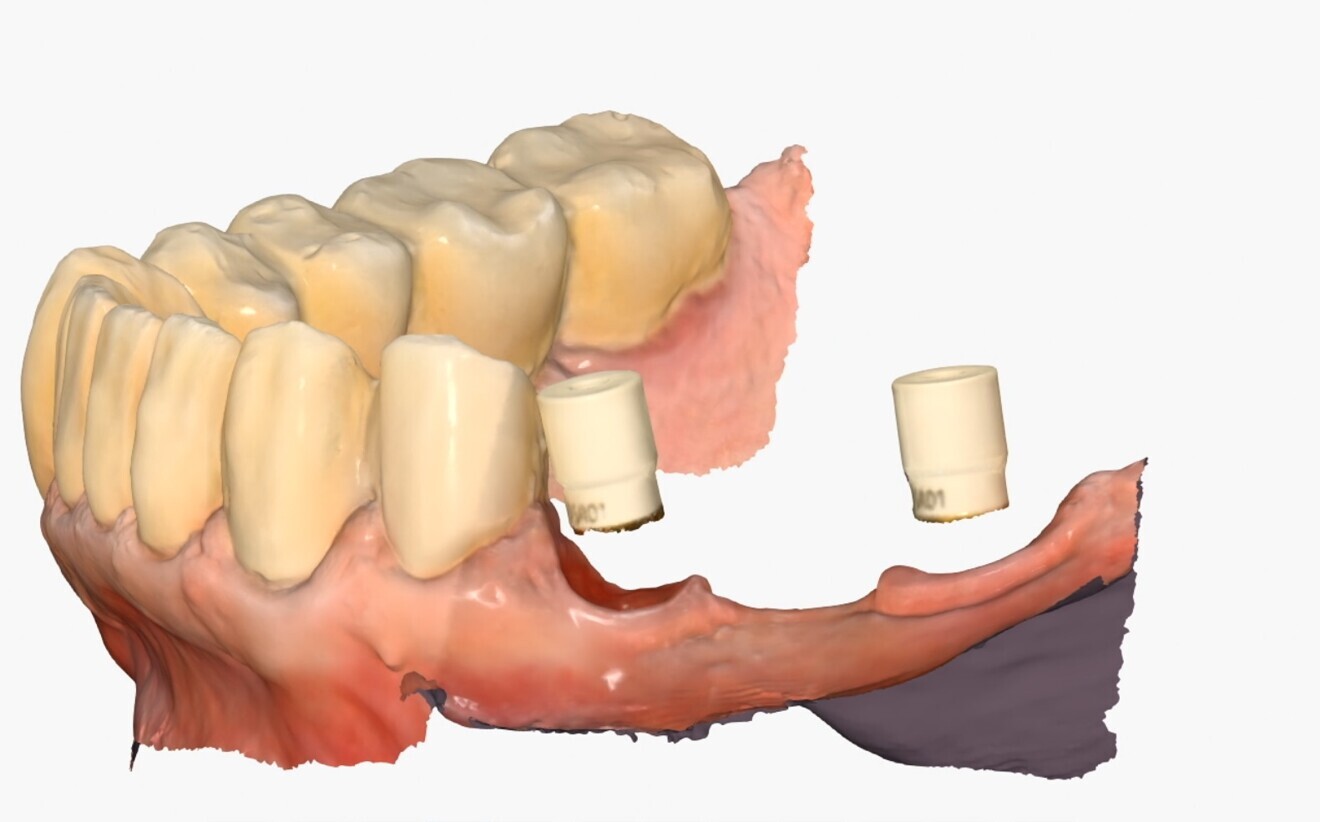

Design Once the STL file of the scan had been obtained, the prosthesis was digitally designed in the RealGUIDE CAD+ software (3DIEMME), according to the following criteria:

precise fit on the ProCam Ti-bases;

passivity of the structure to reduce stress;

occlusion optimisation; and

natural aesthetics through advanced design.

The implant base was then fabricated using Ti-base custom interfaces. A key technical detail comes into play here: the ability to take advantage of a special 50 μm printing offset, designed to ensure the appropriate space for the cement and optimise the accuracy of fit between the 3D-printed part and the Ti-base. This seemingly minor detail turned out to be essential for achieving effective cementation, eliminating any tension and ensuring perfect adhesion of the anatomical part to the implant base. The ability to modify the design in real time made the design phase extremely efficient (Figs. 4a-c). The use of CAD/CAM technologies in fixed implant prosthetics has shown excellent results in terms of precision and fit.3

Figs. 14a–c:: Bridge design in RealGUIDE CAD+.

Fig. 4b

Fig. 4c